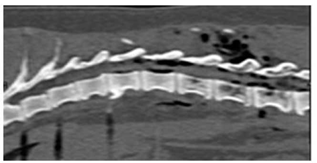

Se realizó un estudio de tomografía helicoidal multicorte (TEM) de columna Tora-co-lumbar realizado en posición supina, con adquisición volumétrica de 1,0 mm y cortes de 5 mm desde T8 a S1. En la TEM se identificó alineación longitudinal y curvatura de columna toraco lumbosacra anteroposterior de aspecto conservado, sin observarse signos en relación a listesis ni fracturas. Se evidenció aire intrarraquídeo compatible con Neumorraquis y enfisema de partes blandas pre y paravertebrales toraco lumbares, Dicho producía cambios compresivos sobre el cordón medular (Figuras 2-4). Sobre la base de los hallazgos por TEM y el mal pronóstico debido al severo daño neurológico, los responsables del paciente tomaron la decisión de realizar la eutanasia.

El NR puede ser clasificado como interno (intradural) y externo (extradural). El NR externo generalmente no produce alteraciones, sin embargo, el NR interno suele relacionarse con procesos traumáticos encefálicos y es un indicador de lesión grave11. La localización y distribución del aire dentro del canal espinal dependerá del sitio de disección del aire, del volumen de aire intraespinal, de la capacidad del espacio intraespinal y el posicionamiento del paciente. En la NR externa, el aire epidural generalmente se ubica en la región epidural dorsal, ya que es menos resistente debido a la menor cantidad de tejido conectivo, esto al compararlo con la red vascular ventral12. La TEM, es la herramienta de elección para el diagnóstico de esta lesión1. Sin embargo, la diferenciación entre un NR intra y extradural puede ser complicado, por lo que es indispensable realizar el monitoreo del estado neurológico del paciente.